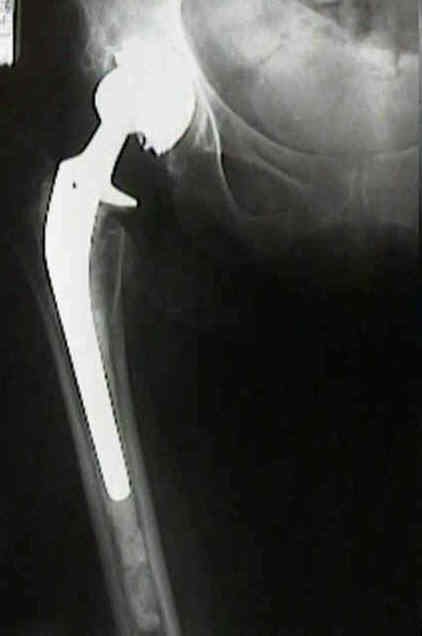

Loosening of Press Fit Acetabular Components

radiographic signs of ingrowth fixation

- absence of radiolucent lines

- presence of a superolateral buttress

- medial bone stress-shielding

- radial trabeculae

- inferomedial buttress

radiographic signs of loosening

- radiolucent lines that initially appeared after two years

- progression of radiolucent lines after two years

- radiolucent lines in all three zones

- radiolucent lines 2 mm or wider in any zone

- migration

- loosening is present w/ more than 2 mm of migration (either horizontal or vertical);